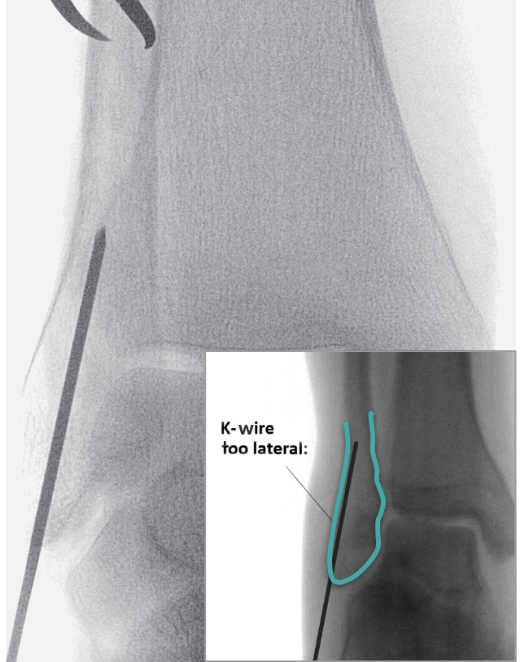

![]() |